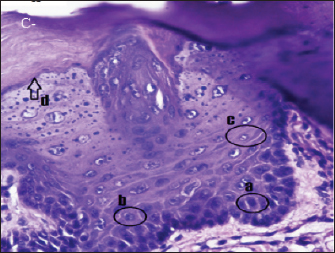

Fig. 5. Histopathological appearance of the rat tongue epithelium in group T3, microscope at ×400. (a) irregular polygonal cell shape in the spinosum layer; (b) oval cell shape in the granulosum layer.

The histopathological appearance of the rat tongue epithelium in the T3 group was close to that of normal epithelium. It is characterized by regular stratification cells. Variations in the shape and size of the nucleus are slight. Hyperchromatic nuclei are found in the basal and parabasal layers. Irregular polygonal cell shapes in the spinosum layer and oval cell shapes in the granulosum layer were also seen in this group (Fig. 5).

In several visual fields, cells in the T3 group had decreased dysplasia, and their condition was similar to that of the negative control group. This suggests that C. cinerariifolium leaf extract at a concentration of 200 mg/kg bw can effectively lower the degree of dysplasia in the oral epithelium. Differences in the terpenoid and flavonoid content of extract and the degree of dysplasia between the treatment groups were reasonably considerable. Other studies have shown that terpineol component in the extract has an anticancer effect by inhibiting the signaling of the transcription factor NF-kB in tumor cells, hence decreasing gene expression in malignancies (Hassan et al., 2010). Terpenoids also function as anticancer agents in human oral cancer cell lines by inducing cell cycle arrest and death in OSCC cells via caspase cascade (Kim et al., 2022). In the extract of C. cinerariifolium leaf, there is also the flavonoid kaempferitin, which can boost the production of the p53 oncogene protein, hence promoting an increase in apoptosis (Siddiqui et al., 2020). The process of inhibiting the production of oncogene proteins and enhancing the expression of tumor suppressor genes can stop aberrant cell proliferation and lower the severity of dysplasia. According to Mutiah et al. (2020), 96% ethanolic extract of C. cinerariifolium (Trev.) leaf based on in silico analysis contains glutamic acid in hydrogen bonds, which inhibits tumor development by blocking angiogenesis.